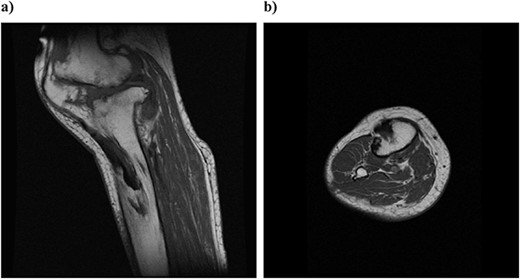

Plain radiography immediately after the surgery: (a) front and (b) lateral side. A slight dilation of the medial joint space is observed.

At 3 years postoperatively, the patient could walk independently. Her extension and flexion were − 5° and 120°, respectively, her KS score was 83 points, and her KS-F score was 90 points. Radiography showed a slight valgus position, with some lateral subluxation of the patella, but the patient reported no problems with her activities of daily living (Fig. 5).

Outcome at 3 years after surgery on plain radiography: (a) standing front and (b) side. The patella is laterally subluxated in a slight valgus position.